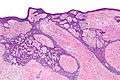

Basal-cell carcinoma, nodular type

To diagnose basal cell carcinomas, a skin biopsy is performed for histopathologic analyses. The most common method is a shave biopsy under local anesthesia. Most nodular basal cell cancers can be diagnosed clinically; however, other variants can be very difficult to distinguish from benign lesions such as intradermal naevus, sebaceomas, fibrous papules, early acne scars, and hypertrophic scarring.[4]

Histopathologic classification

The histopathologic classification includes:[5][6]:646–650

- Nodular basal cell carcinoma (also known as "classic basal-cell carcinoma") most commonly occurs on the sun-exposed areas of the head and neck.[5]:748[6]:646

- Cystic basal cell carcinoma is morphologically characterized by dome-shaped, blue-gray cystic nodules.[6]:647

- Cicatricial basal cell carcinoma (also known as "morpheaform basal cell carcinoma," and "morphoeic basal cell carcinoma") is an aggressive variant with a distinct clinical and histologic appearance.[5]:748[6]:647

- Infiltrative basal cell carcinoma is an aggressive type characterized by deep infiltration.[6]:647

- Micronodular basal cell carcinoma is characterized by a micronodular growth pattern.[6]:647

- Superficial basal cell carcinoma (also known as "superficial multicentric basal-cell carcinoma") occurs most commonly on the trunk and appears as an erythematous patch.[5]:748[6]:647